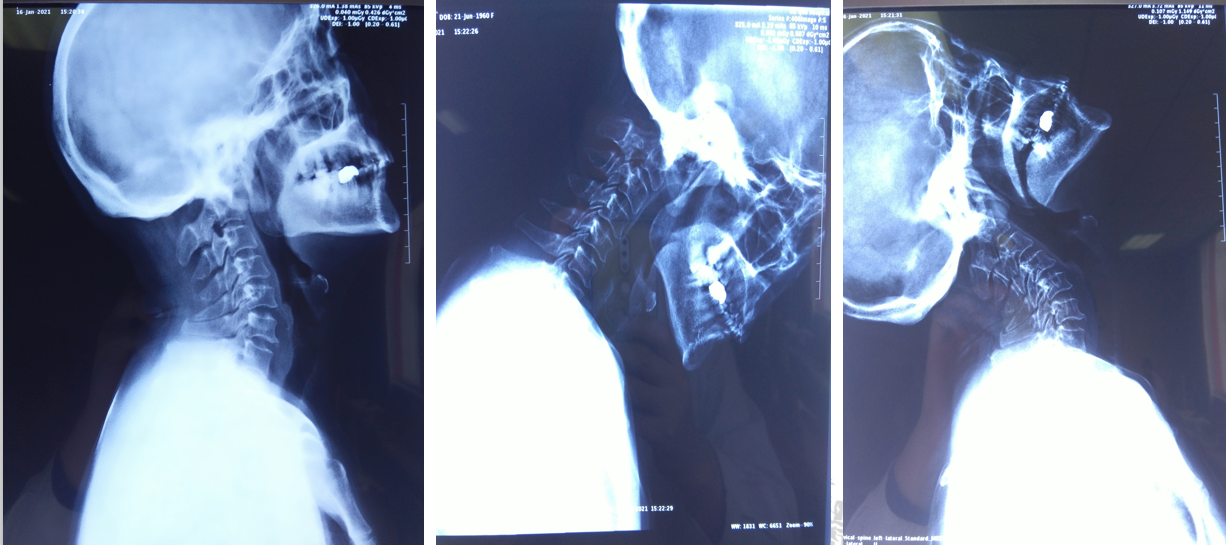

颈椎CT:

颈椎退行性变,C2/3、C3/4、C4/5、C5/6、C6/7椎间盘突出并C4/5水平椎管狭窄;符合颅底凹陷症合并寰枕融合,寰枢关节脱位CT表现。

颈部血管CTA:

颈动脉硬化并多动脉狭窄,以右侧颈内动脉起始处为著,呈中度狭窄。

颈髓MRI:

颅底凹陷症、寰枕融合;寰枢关节脱位并延髓脊髓变性或损伤;颈椎退行性变;C2/3、C3/4、C4/5、C5/6、C6/7椎间盘突出并C4/5水平椎管狭窄。

患者术前部分影像学资料

影像学资料显示寰枢椎脱位,脊髓受压明显